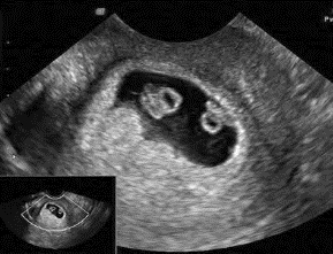

图34-9 孕40天单卵双胎妊娠声像图

子宫内有一妊娠囊其中有两个胚芽回声